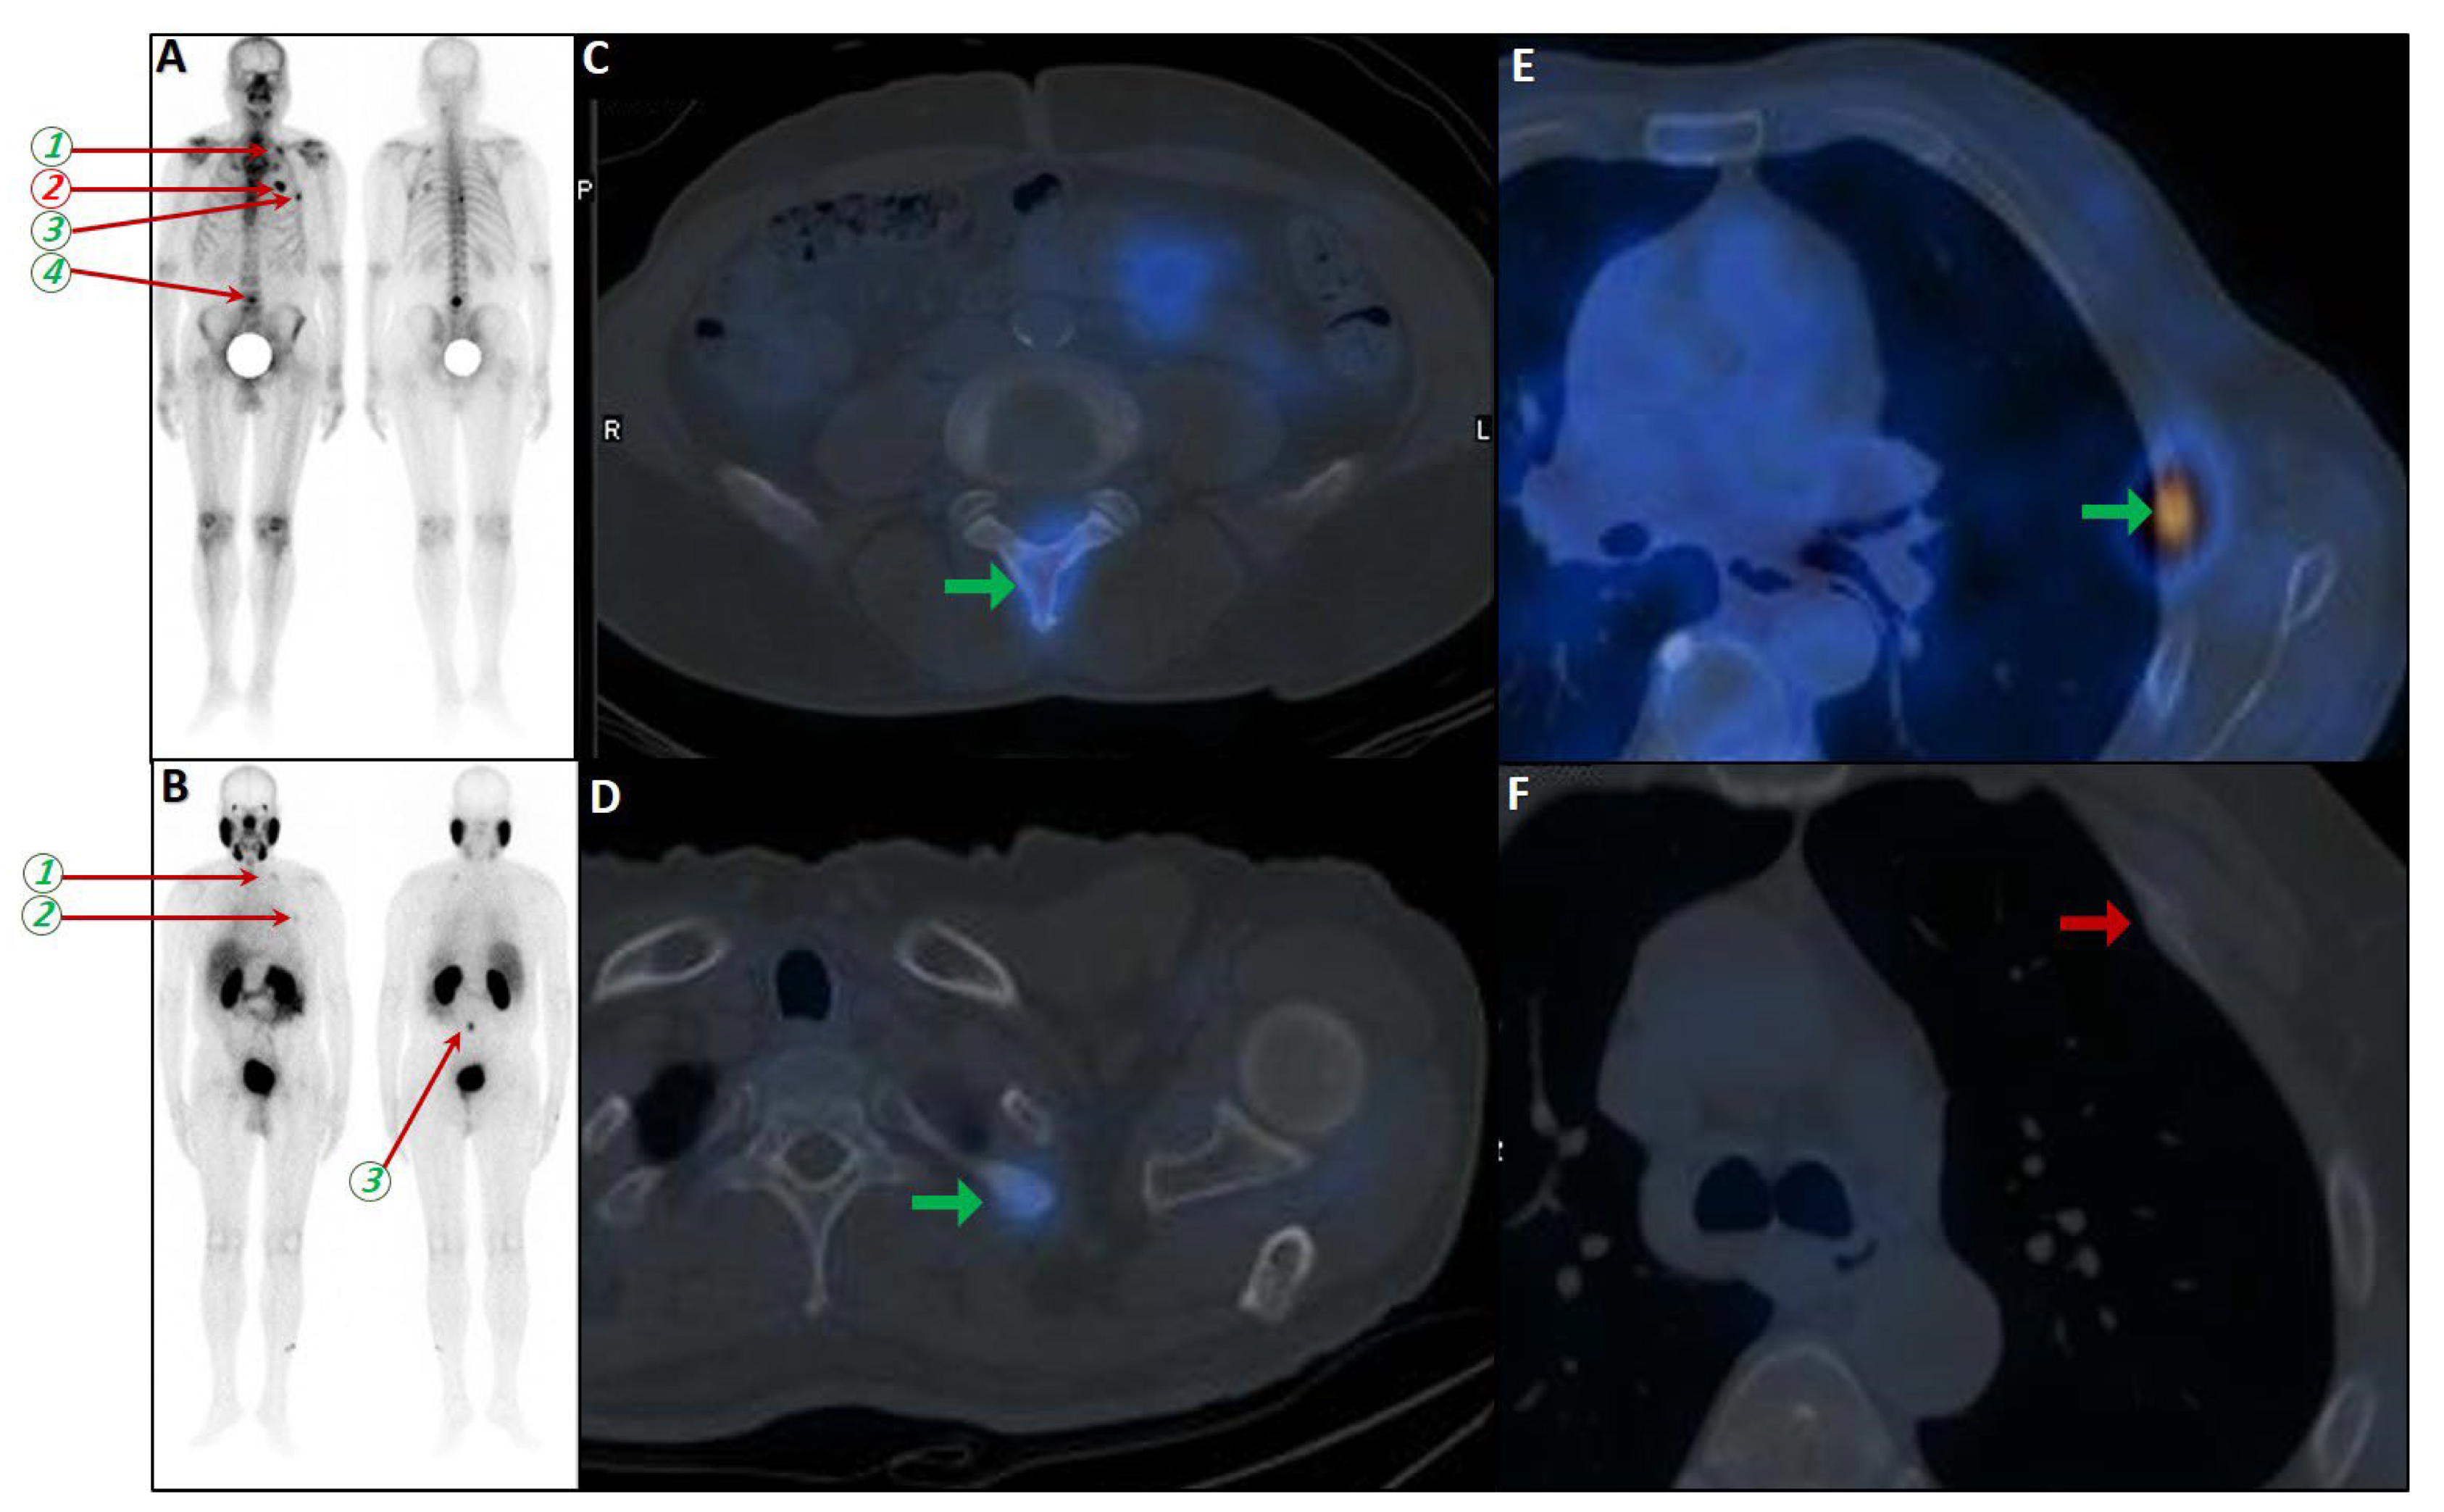

Figure 4.

Partial concordance of PSMA and bone scan. A 66-year-old man with prostate adenocarcinoma (biopsy Gleason score 4 + 5 in 8/12 cores, serum PSA = 45 ng/dL) was referred for staging. Bone scan showed four foci of increased osteoblastic activity, three in the ribs (non-consecutive, anterior/lateral aspect) on the left side as well as L5 vertebra (A). Whole-body 99mTc-PSMA scan SPECT/CT (B) showed PSMA-avid lymph node metastases in the left external iliac and left common iliac (not shown). Skeletal metastases (green arrow) in the L5 spinous process (C) and posterior aspect of the left 2nd rib (D) and lateral 5th left rib (E), and non-PSMA-avid fracture in the 4th left rib (red arrow, (F)). The patient was down-staged from polymetastatic high-volume disease to oligometastatic disease.